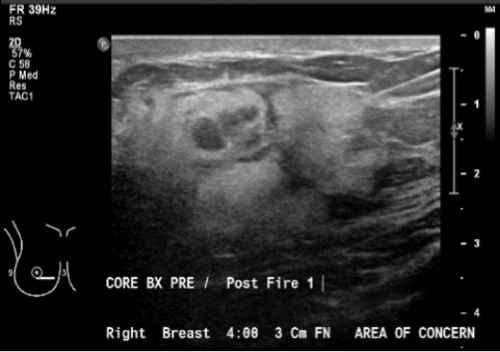

Over the next six months, the patient reported enlargement of the mass and slight tenderness. A right breast ultrasound was suggestive of a 1.5 cm fibroadenoma. One month later, a diagnostic mammogram demonstrated diffusely increased parenchymal density and skin thickening but no dominant mass. Repeat ultrasound demonstrated a 5 cm hyperechoic area with a 1.2 cm central area of hypoechogenicity, a series of nodules, and "intense surrounding blood flow" (Figure 1). Core needle biopsy revealed a vasoformative lesion, favoring a hemangioma. In the operative note of the subsequent excisional biopsy, "extremely large vessels circumferentially around the mass" were noted. After a pathologic review locally and at a tertiary academic medical center, the final diagnosis was a well-differentiated angiosarcoma of the breast, which measured 1.2 cm by gross examination. Although the surgical margins were not specifically addressed, completion mastectomy was recommended.

Figure 1. Targeted Ultrasound of Right Breast Taken before Biopsy. Published with Permission

A) Hyperechoic mass with nodules within breast parenchyma

B) Blood flow within and surrounding mass